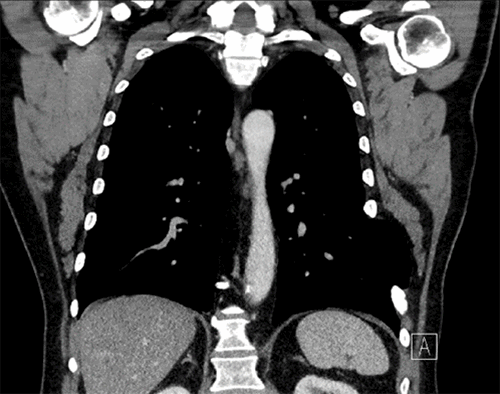

A 72-year-old man presented to the emergency department with shortness of breath, dyspnea on exertion, a hacking, productive cough, and left-sided chest pain. He had no history of trauma. He had a 50-pack/year smoking history and continued to smoke after being placed on home oxygen. His admitting chest radiograph revealed a small left pleural effusion and changes consistent with COPD (Figure 1). A previous chest radiograph was reviewed and revealed only changes of COPD and no evidence of left diaphragm eventration. He was hospitalized for nebulizer therapy, acute administration of intravenous steroids, and to rule out an acute coronary syndrome. During his admission, he began complaining of abdominal distension and constipation and continued to have a chronic cough. On physical examination, he was obese (BMI 33.7 kg/m2) with a pulse of 102 and labored breathing. Chest auscultation revealed diffuse rhonchi with diminished breath sounds at the left lung base. His abdomen was distended, tympanitic, and diffusely tender. There was ecchymosis along the left flank extending to the left lower quadrant, consistent with Grey Turner sign. Laboratory studies revealed a white blood cell count of 18,300/μL, and arterial blood gas showed a pH of 7.34, pCO2 of 42 mmHg, and pO2 of 60 mmHg on 5 L/min by nasal cannula. An electrocardiogram demonstrated sinus tachycardia but no ischemia. A plain film now revealed loops of bowel in the left hemithorax (Figure 2).

Figure 2. Plain radiography of the chest immediately before surgery now revealing an air-filled structure in the left hemithorax with valvulae conniventes suggestive of bowel loops and blunting of the left costophrenic angle suggestive of a large left-sided pleural effusion